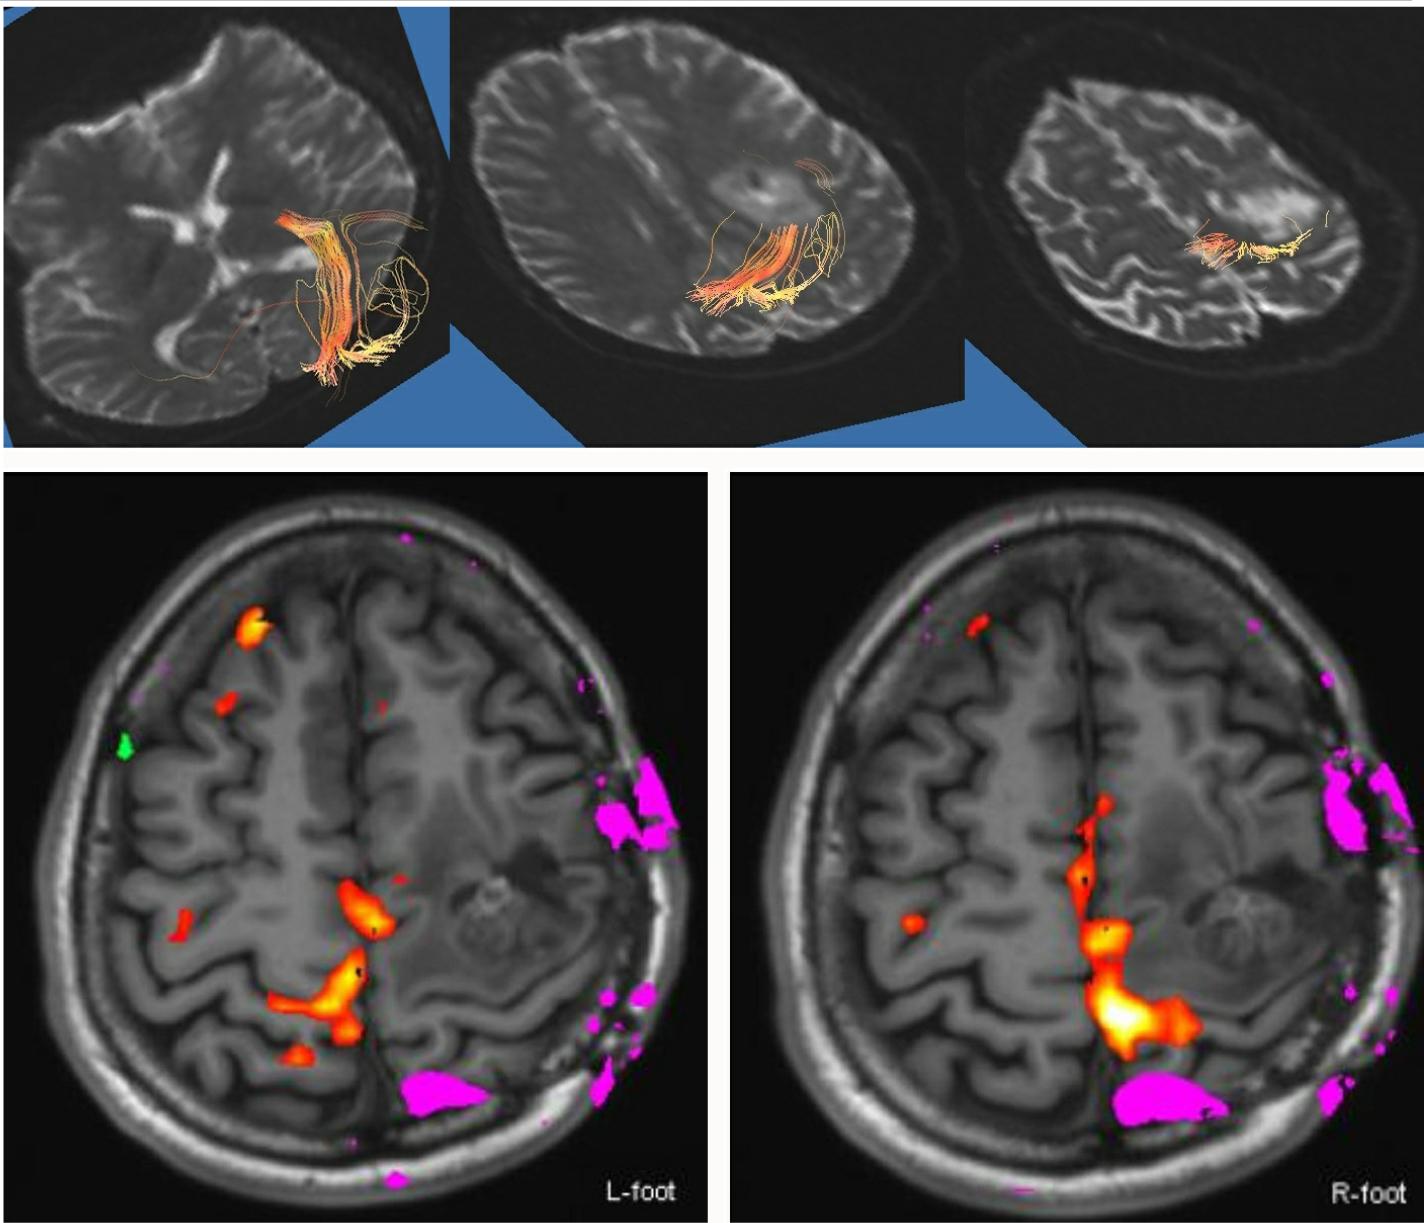

Initial symptom was gradually deteriorating right hand monoparesis of four months duration. Radiological examination showed a round heterogeneous mass located at the ventral side of precentral gyrus in the left frontal lobe (Figure 1, upper). Intraoperative motor evoked potential and somatosensory evoked potential mapping successfully indicated the central sulcus and precentral gyrus in the operative field. Internal decompression of the tumor was performed through minimum corticotomy to avoid damage of the eloquent areas of the brain. Histopathological diagnosis was anaplastic ependymoma and 80% of the enhanced lesion was removed (Figure 1, lower). Adjuvant conventional radiotherapy was added. She recovered motor function in the right upper extremity. Two years after the initial surgery, she presented with a progressively worsening right upper extremity (U/E) paresis, manual muscle testing (MMT) 3. Neuroimaging investigations confirmed tumor regrowth. A second surgery was scheduled. Prior to the second surgical treatment, functional magnetic resonance imaging (fMRI) and tractography confirmed the right motor function to be located in the left precentral gyrus and connected to pyramidal tract (Figure 2). Internal decompression was performed again with the aim of preserving and recovering her left U/E function. Histopathological diagnosis was as same as the initial surgery, but MIB-1 labeling index increased. After the second surgery, rapid local regrowth of the tumor was observed. Two further surgeries for internal tumour decompression and Ommaya reservoir placement for evacuation of fluid in the tumour removal cavity were necessary in one year. Temozolomide, procarbazine and interferon-beta were not effective for tumor control.

MRI before second operation. Tractography which was caliculated by volume one showing corticospinal tract located at parietal side of the lesion (upper). Functional MRI by moving foot joint showing that hot spot of lower left and lower right looks almost as a mirror image.